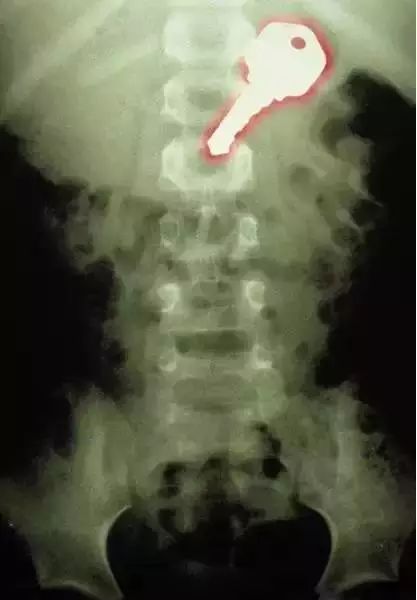

13、这张有色的X光片显示,这个7岁的男孩吞下了一枚钥匙。